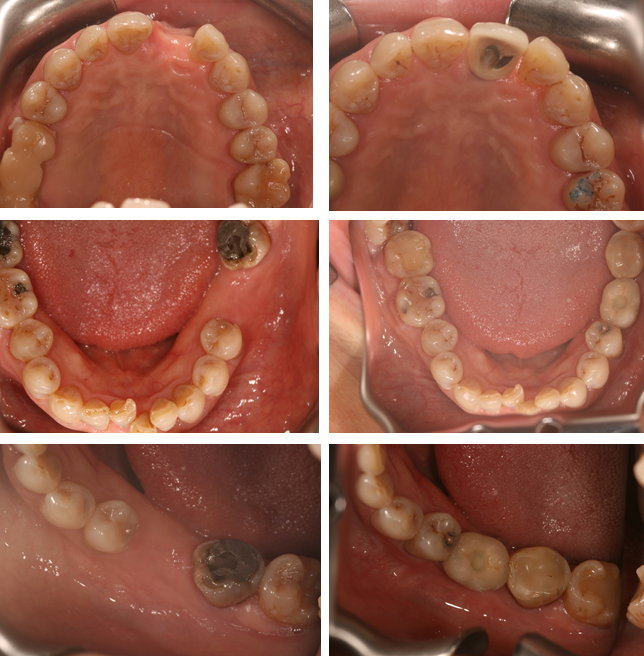

Here at Aesthetic Dental Zone we embrace new concepts, guided implant surgery provides a solution where doctors can plan an implant virtually, and then accurately place an implant in the safest, predictable and efficient manner.

With guided surgery, we place the implant for the best aesthetic result and can predict accurately how much room will be needed for the crown and for any veneered superstructure that may go over the abutment.

From a single missing tooth to an edentulous jaw. It aids your Doctor to diagnose, plan the treatment and place your implants based on restorative needs and surgical requirements.

Following an initial Implant Consultation and CBCT scan (3D Scan of your jaw) we can get to work on your specific Implant case.Guided Implant Surgery takes away the need to be too invasive when placing your dental implants.

It is extremely accurate, more comfortable and the healing time is reduced.Guided Implant Surgery is a state of the art technology, trust in us to make your implant process as simple and easy as possible.